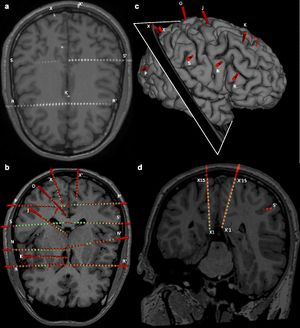

Multiple Time Courses of Somatosensory Responses in Human Cortex

Publication: Neuroimage. 2017 Dec 14;169:212-6. PMID: 29248698 Authors: Avanzini P, Pelliccia V, Lo Russo G, Orban GA, Rizzolatti G. Institution: CNR Institute of Neuroscience, National Research Council, Parma, Italy Abstract: Here we show how anatomical and functional data recorded from patients undergoing stereo-EEG can be used to decompose the cortical processing following nerve stimulation in different stages characterized by specific topography and time course. Tibial, median and trigeminal nerves were stimulated in 96 patients, and the increase in gamma power was evaluated over 11878 cortical sites. All three nerve datasets exhibited similar clusters of time courses: phasic, delayed/prolonged and tonic, which differed in topography, temporal organization and degree of spatial overlap. Strong phasic responses of the three nerves followed the classical somatotopic organization of SI, with no overlap in either time or space. Delayed responses presented overlaps between pairs of body parts in both time and space, and were confined to the dorsal motor cortices. Finally, tonic responses occurred in the perisylvian region including posterior insular cortex and were evoked by the stimulation of all three nerves, lacking any spatial and temporal specificity. These data indicate that the somatosensory processing following nerve stimulation is a multi-stage hierarchical process common to all three nerves, with the different stages likely subserving different functions. While phasic responses represent the neural basis of tactile perception, multi-nerve tonic responses may represent the neural signature of processes sustaining the capacity to become aware of tactile stimuli. "...multimodal scenes were built with the 3D Slicer software package." |